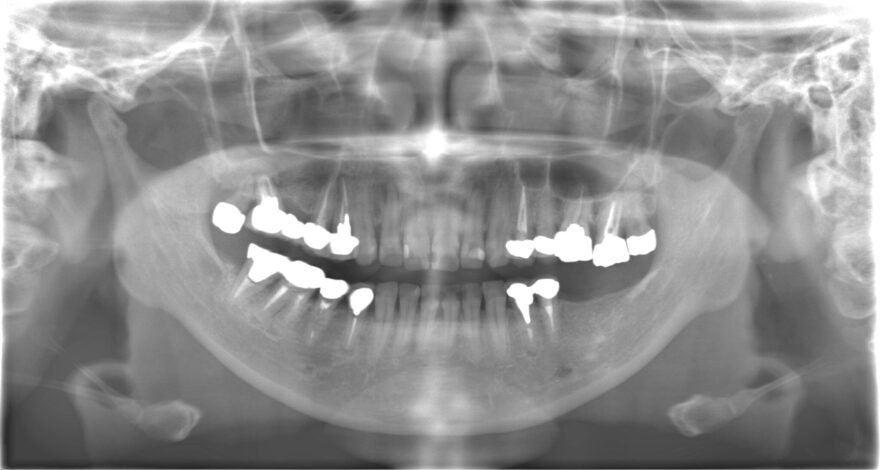

どこで噛んでいいか分からない:40代女性

全体的な噛み合わせが狂ってしまい、どこで噛んでいいか分からない状態でした。

8本のインプラント治療と16本のセラミック治療で、しっかり上下の歯が噛み合う状態にしました。

治療期間

1年

費用

奥歯インプラント8本→3,520,000円(税込)

《1本あたり440,000円(税込)》

前歯プレミアムセラミック12本→1,980,000円

《1本あたり165,000円(税込)》

奥歯プレミアムセラミック10本→1,430,000円

《1本あたり143,000円(税込)》

ファイバーコア5本→110,000円(税込)

《1本あたり22,000円(税込)》

前歯精密根管治療2本→220,000円

《1本あたり110,000円(税込)》

咬合再構成(全ての仮歯代とデジタルデザイン含む)24本→792,000円

《1本あたり33,000円(税込)》

総額 8,052,000円(税込)